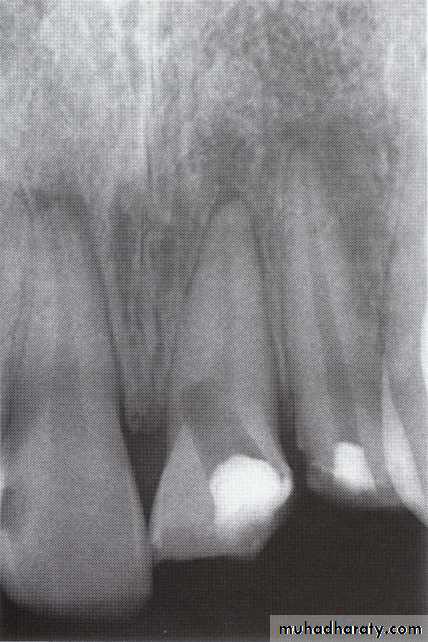

• Access through a small or flattened (disk-like) pulp chamber in a multirooted tooth.

• Proper reading of the preoperative (diagnostic) radiograph to get information about the size and extent of the pulp chamber and internal changes (calcification or resorption).